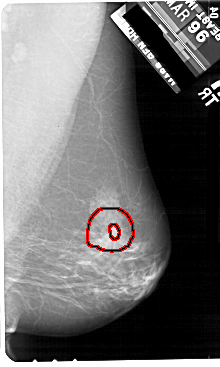

A_1908_1.RIGHT_MLO

RIGHT_CC LINES 5491 PIXELS_PER_LINE 2971 BITS_PER_PIXEL 12 RESOLUTION 43.5 OVERLAY

FILE: A_1908_1.RIGHT_CC.OVERLAY

TOTAL_ABNORMALITIES 1

ABNORMALITY 1

LESION_TYPE MASS SHAPE IRREGULAR MARGINS SPICULATED

ASSESSMENT 5

SUBTLETY 4

PATHOLOGY MALIGNANT

TOTAL_OUTLINES 2

BOUNDARY

CORE